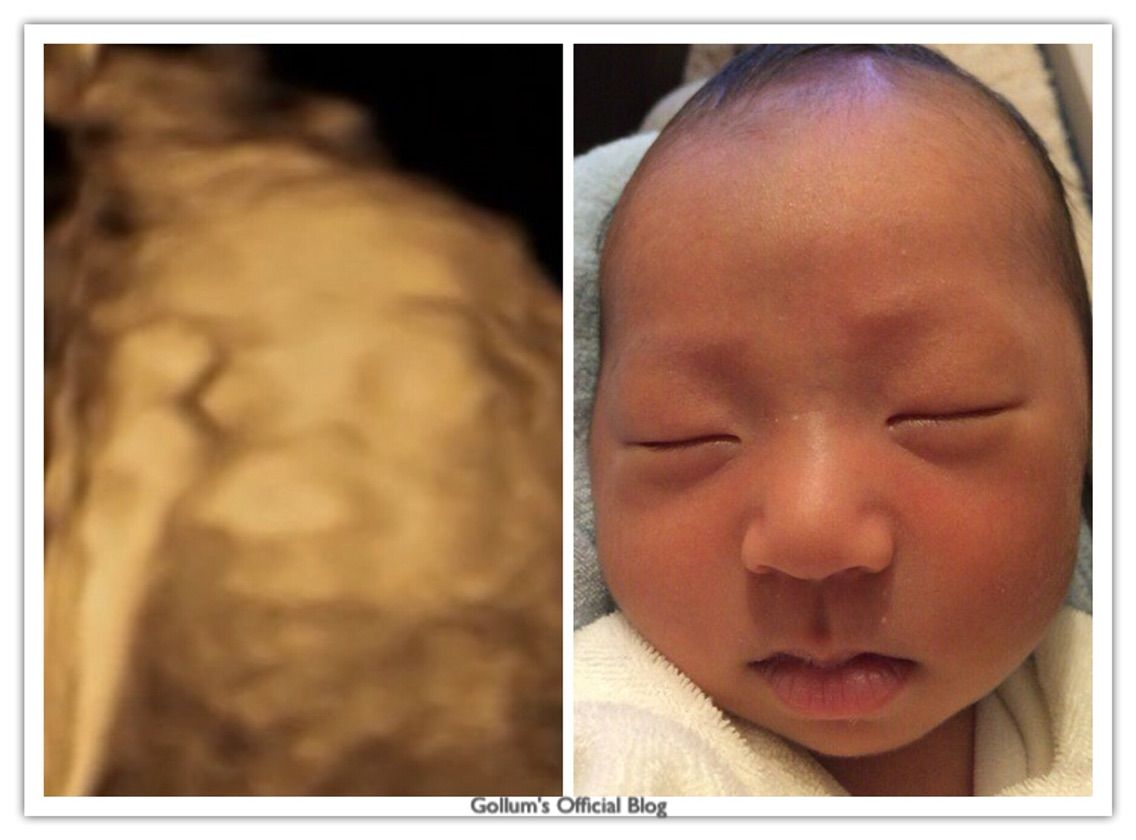

画像ありエコー写真と実際の顔を徹底比較!!4Dエコー撮影 お鼻の形は似てますがエコー写真ほど大きくはありません! 38週3日の4Dエコー 赤ちゃん大きくなっているのであまりよく見えなくなってきています。 補足 初めて13週に4dエコーを撮ったとき. 4Dエコーと実際の顔 こんばんは。 琉偉さんが妊娠中に4Dエコーというものを体験しました。 だそうです。 お腹の中でだんだん成長していく様子を残すことが出来ます。 こんな写真も。 ちなみに横浜市立市民病院には4Dエコーの設備がありません. 赤ちゃんの3d 4dエコー写真 実際の顔と比較してみたら似てた 旅 千葉県の北森ペット病院は現代社会に寄り添った動物のライフスタイルに重きを置いて、様々な疾患の研究を進めています。胎児の3D、胎生期の器官形成、胎児の心臓等、興味がつきません ;.

パパパッとパパ 4Dエコーと実際の顔を生後7日間の徹底比較! 画像で検証 息子が生まれる前、検診に行って4Dエコーの画像を見ては「パパとママどっちに似てるんかな」とか「イケメンかな」とかいろいろと妄想を膨らませていました。 ちなみにその. 出産前は、4dエコー(3dエコー)の写真を見つめながら、まだ見ぬわが子に思いを馳せたものです。 実際、エコー写真と産まれた後の顔は似ているのか? 4dエコー(24週・27週)/3dエコー(36週)と生後3日の写真を比較してみました。 スポンサーリンク. 画像ありエコー写真と実際の顔を徹底比較!!4dエコー撮影 でも4dエコーしてもらった時は 鼻がでかすぎて 、えっ?ってビックリしちゃいました。笑 エコー写真がどれくらい正確なのか産まれた息子と比較してみたいと思います!.

画像ありエコー写真と実際の顔を徹底比較!!4dエコー撮影 目はあまり似ていませんが鼻から口にかけては似ているような気がします。 31週3日の4dエコー 見た瞬間、鼻でかーーー!!って驚きま. 4Dエコーで初めて見たわが子の顔! 先生が撮った最高の1枚 産後に発症! むくみの裏に潜んでいた「妊娠高血圧症候群」 「常位胎盤早期剥離」で、母子ともに命の危機に! 退院後は帯状疱疹&産後うつまで 4歳の男の子と1歳の女の子を子育て中の 4dエコーとは、従来の2dや3d 実際に. エコー検査におけるダウン症児の顔の特徴について エコー検査では様々なことが調べられるのですが、 エコーの画像において顔の特徴が解るのかと言うと、1つだけ大きな特徴があります。 ダウン症児には典型的なものなのですが、.

エコー写真が ブサイク 実際の顔とどれくらい違うのか検証 La Sana

4dエコーと実際の顔を生後7日間の徹底比較 画像で検証 パパパッとパパ

画像あり エコーと実際の赤ちゃんはどのぐらい違う いずれは晴れる